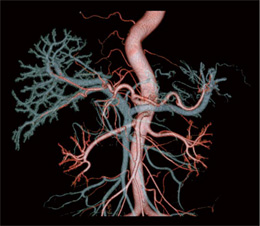

3.VR

VR(Volume Rendering)は,形状診断には欠かせない画像である。近年はカテーテルによる血管撮影の代替となりうる画像が提供可能である。脈管の走行を把握するため,観察したい血管のみの抽出がAdd Vessel機能により簡便に行える。また,肝動脈と門脈を重ね合わせたり,MPR像に重ね合わせたりと簡便に加工が可能である(図7,8)。 |

図7 肝動脈と門脈の重ね合わせ画像 |